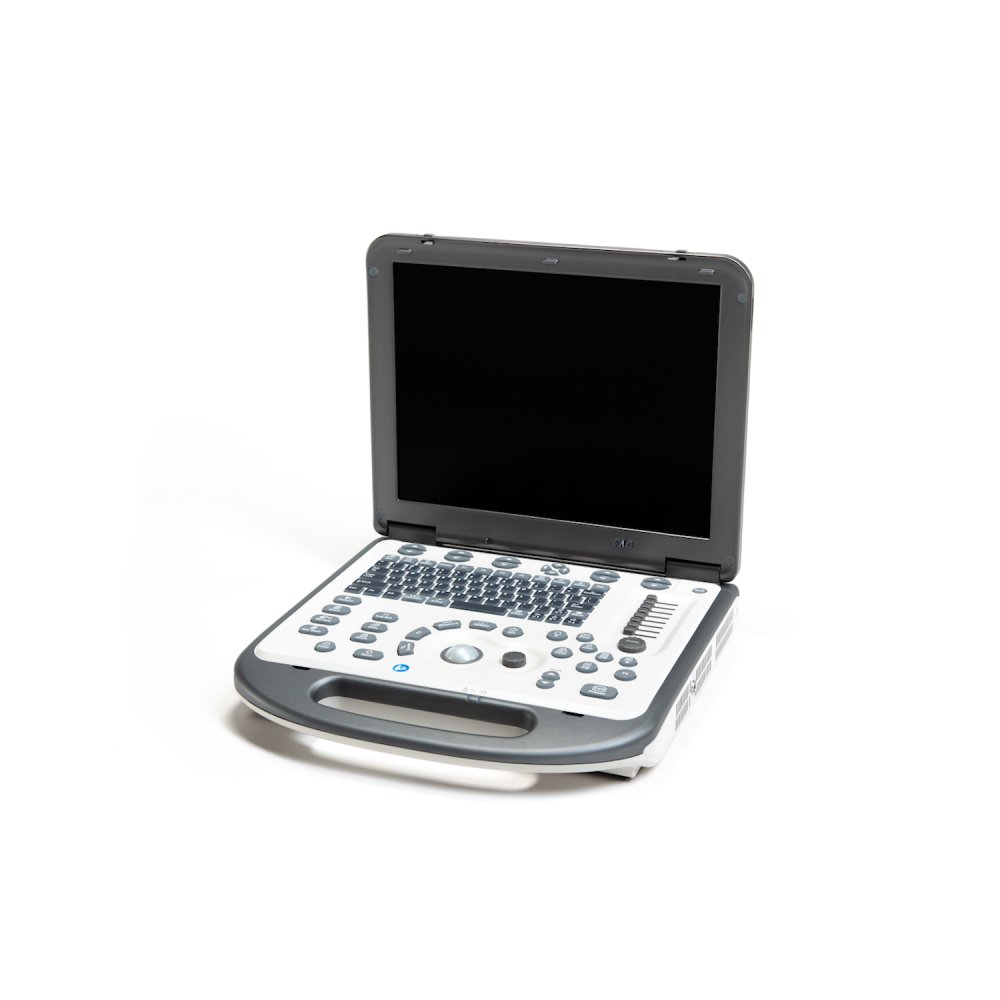

УЗИ аппараты

УЗИ аппараты

УЗИ аппараты

УЗИ аппараты

УЗИ аппараты

УЗИ аппараты

УЗИ аппараты

УЗИ аппараты

УЗИ аппараты

УЗИ аппараты

УЗИ аппараты

УЗИ аппараты

УЗИ аппараты

УЗИ аппараты